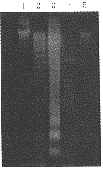

3 蟾蜍灵诱导细胞DNA裂解 如图1所示,0.010,0.100μmol/L 蟾蜍灵作用HL-60细胞24h,琼脂糖凝胶电泳获得清晰的凋亡特征性梯形条带。

1:蟾蜍灵 0.001μmol/L; 2:蟾蜍灵 0.010μmol/L;

3:蟾蜍灵 0.100μmol/L;4:分子量标准(pBR322 DNA/BstN Ⅰ); 5:对照组

图1 蟾蜍灵诱导HL-60细胞DNA裂解的电泳结果4 外源化合物对细胞凋亡的调节作用 蟾蜍灵与放线菌酮或ZnCl2共同作用HL-60细胞,电泳结果显示蛋白质合成抑制剂放线菌酮对蟾蜍灵诱导的凋亡没有影响,说明凋亡的发生不需要新的蛋白质的合成,而核酸内切酶抑制剂ZnCl2抑制了蟾蜍灵诱导的细胞凋亡(图2)。